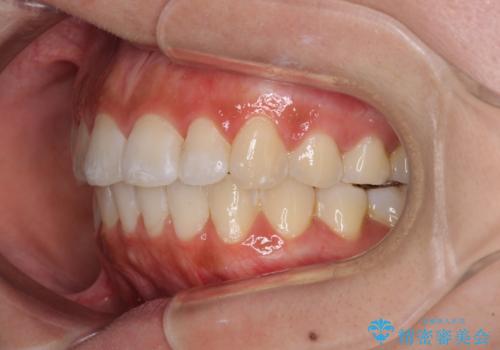

前歯のデコボコが気になる インビザラインによる矯正治療

- 上下前歯のデコボコを気にして来院された患者様です。

インビザラインによる上下歯列の拡大と、IPR(歯と歯の間を削る)にるスペースの獲得により、前歯のデコボコを改善することとしました。

しっかりと装着時間を遵守してくださったので、思い通りの歯列に整えることができました。

結婚式前に終了させることができ、患者様には大変満足していただきました。